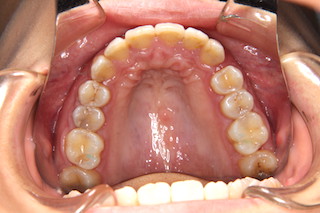

噛み合わせが深く,下の前歯が見えません!

上顎・・前歯には叢生があります

上顎・・見えない位置のインプラントで奥歯を更に奥へと動かします

上顎・・叢生も解消です!